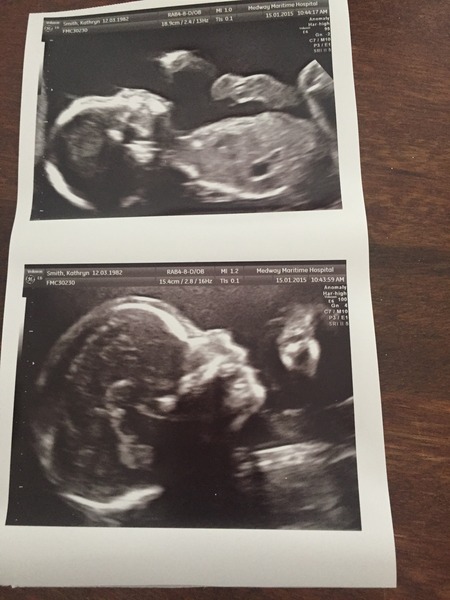

All fine at scan thank god! Have anomaly scan Monday with same sonograper so he had a quick look today and said nothin looks out of the ordinary so hopefully all will be fine Monday too! Thanks for good wishes! Here is a pic of my lil monkey!

Ah, congrats Chook! Lovely pics.

Congrats chookford amazing detail of baby's head!

Thanks jenny yes it was amazing, baby was boxing most of the time it disnt want to be scanned! Grin

Wow so detailed chookford, bet you're thrilled x

Lovely scan chook :)

Congrats chook and you do have lovely pictures!